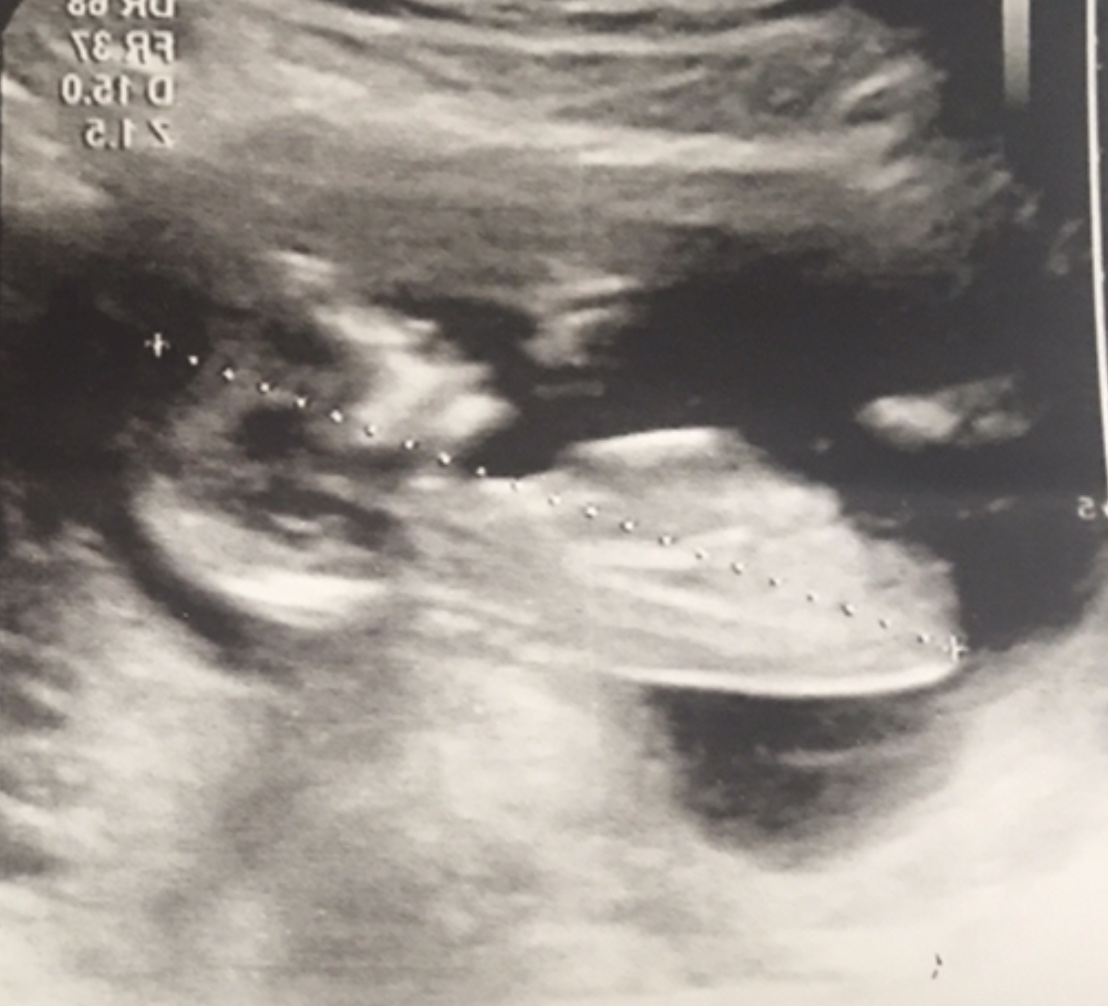

سلام مال منم تشخیص میدید

بیشتر شبیه پسره

به نظرت زاویش موازی نیست برا من؟

برا منم بگید .ممنون